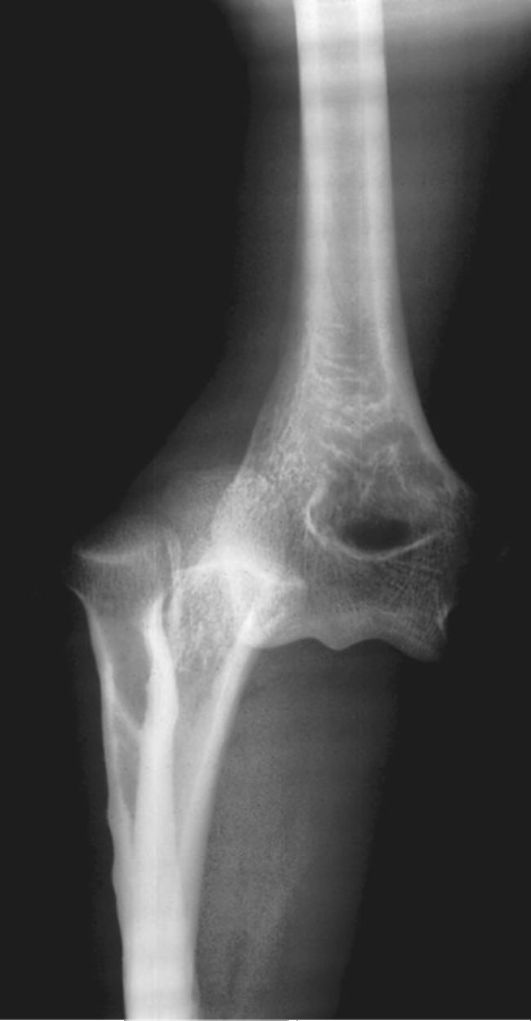

Переломы и вывихи являются одной из самых частых причин направления пациентов на лучевое исследование (чаще всего - рент- генографию). Перелом - это нарушение анатомической целостности кости (рис. 3-10). Вывих - смещение суставных поверхностей костей по отношению друг к другу (рис. 3-11).

Рис. 3-11. Вывих локтевого сустава